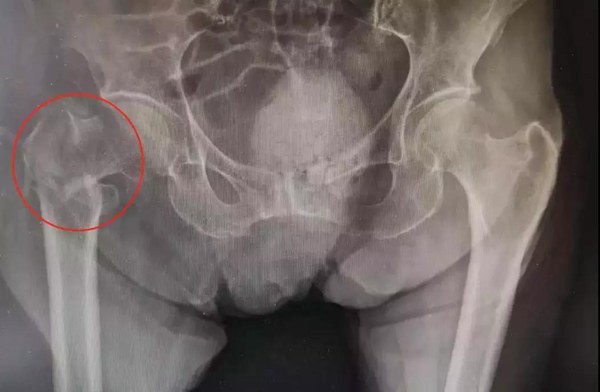

老年人常常都有骨质疏松,稍不留神的一个“屁股蹲”,可能就会造成髋部骨折。黄奶奶就是这髋部骨折中的一类骨折,专业的名字叫做“股骨粗隆间骨折”,也可以简单的理解为“大腿根部骨折”。

△黄奶奶骨折的部位